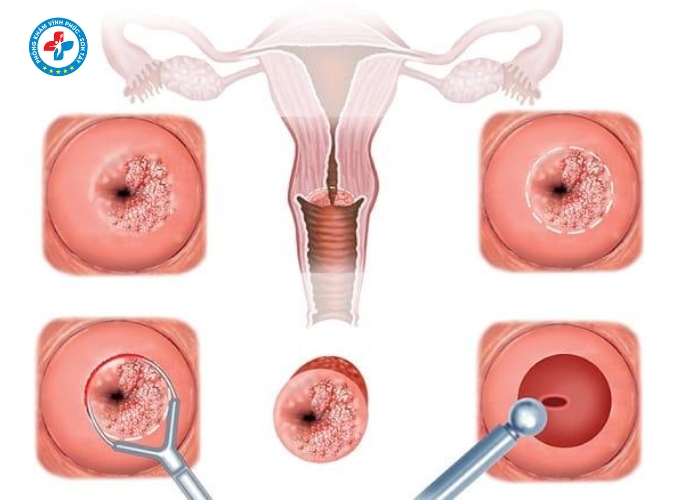

Lộ tuyến cổ tử cung là gì?

Lộ tuyến cổ tử cung là tình trạng các tế bào tuyến bên trong cổ tử cung phát triển và xâm lấn ra mặt ngoài cổ tử cung. Những tế bào này tiết dịch nhiều hơn bình thường, tạo môi trường thuận lợi cho vi khuẩn phát triển.

Dấu hiệu nhận biết lộ tuyến cổ tử cung

Các biểu hiện thường gặp:

- Khí hư ra nhiều, có mùi hôi

- Khí hư màu trắng đục, vàng hoặc xanh

- Ngứa rát vùng kín

- Đau khi quan hệ

- Xuất huyết nhẹ sau quan hệ

Khi nào cần điều trị lộ tuyến cổ tử cung?

- Lộ tuyến độ 2, độ 3